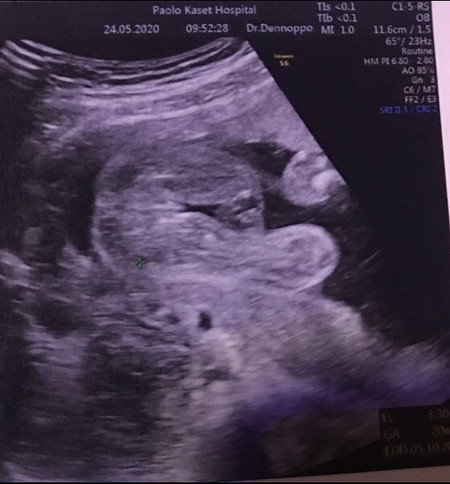

เพศ ญ หรือ ช

ช่วยดูหน่อยคะ ว่าได้ ญ หรือ ช

หมอไม่บอกหรอคะแม่ หมอบอกจะชัวร์กว่าน้าจ้ะ จากภาพไม่เห็นจู๋ เดาว่าญ.ค่ะ

ญ แน่นอน